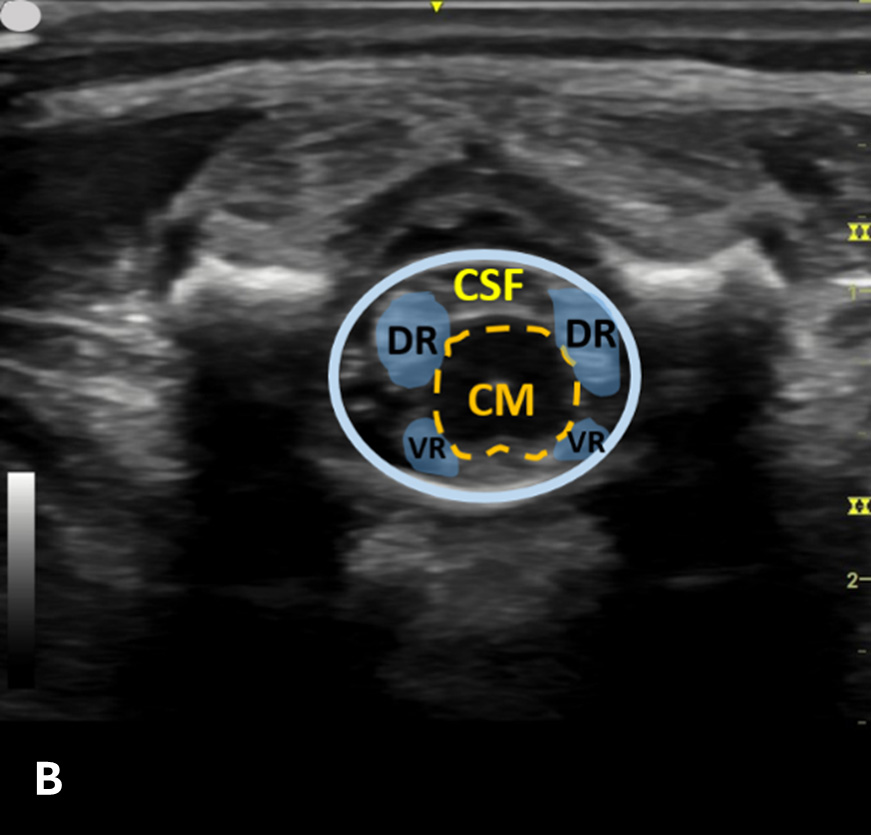

The transverse view should also be obtained to verify landmarks and identify any overlying vessels or hematomas (from prior attempts) to avoid. The transducer is rotated to the transverse position on the lower back and moved caudally over the spinous processes to locate the CM, which is a hypoechoic structure positioned in the center of the spinal canal. At higher levels of the CM, the ventral roots and dorsal roots can be identified, which are surrounded by the anechoic CSF. Next, gradually move the transducer caudally and observe the CM decreasing in size while being encircled by the hyperechoic fibers of the CE. (Figure 2) Once this sonographic landmark is identified, locate the center of the transducer and mark the corresponding area on the skin, aligning it with the center of the spinal cord. Subsequently, draw lines from both markers in both planes and utilize the point of intersection as a guide for inserting the LP needle. To enhance visualization of the spinal cord’s vascular supply, and avoid a space with any overlying vessels that may cause a traumatic tap, it is advisable to apply color Doppler in both the sagittal/longitudinal and transverse views.9 (Figure 3)

Figure 2 - Corresponding US image showing spinal canal structures in transverse view:

Figure 2 - Corresponding US image showing spinal canal structures in transverse view. 2A-B: The caudal portion of the transverse view shows DR (dorsal roots), VR (ventral roots), CSF (cerebrospinal fluid), and CM (conus medullaris). 2C-D: The probe is moved caudally demonstrating the tapered CM (orange dotted circle), CE (cauda equina, hyperechoic structure surrounding the CM) and a pocket of CSF. 2E-F: Demonstrate the disappearance of the CM, and the pocket of CSF becoming larger as the probe was moved caudally. The blue circle is the entire dural sac encircling the spinal canal.